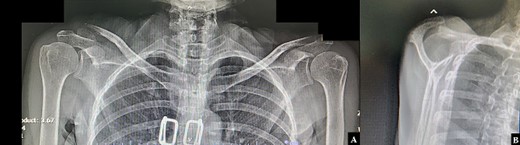

A 61-year-old Thai male presented with notable right shoulder discomfort subsequent to a fall. Radiographic anteroposterior views of both clavicles and a transcapular view of the right shoulder revealed a displaced distal clavicle fracture (Fig. 1A and B). Following deliberation with the patient, closed reduction coupled with coracoclavicular stabilization was chosen for treatment.

Radiographic (A) anteroposterior views of both clavicles and (B) a lateral transcapular view of the right shoulder revealed a displaced right distal clavicle fracture.